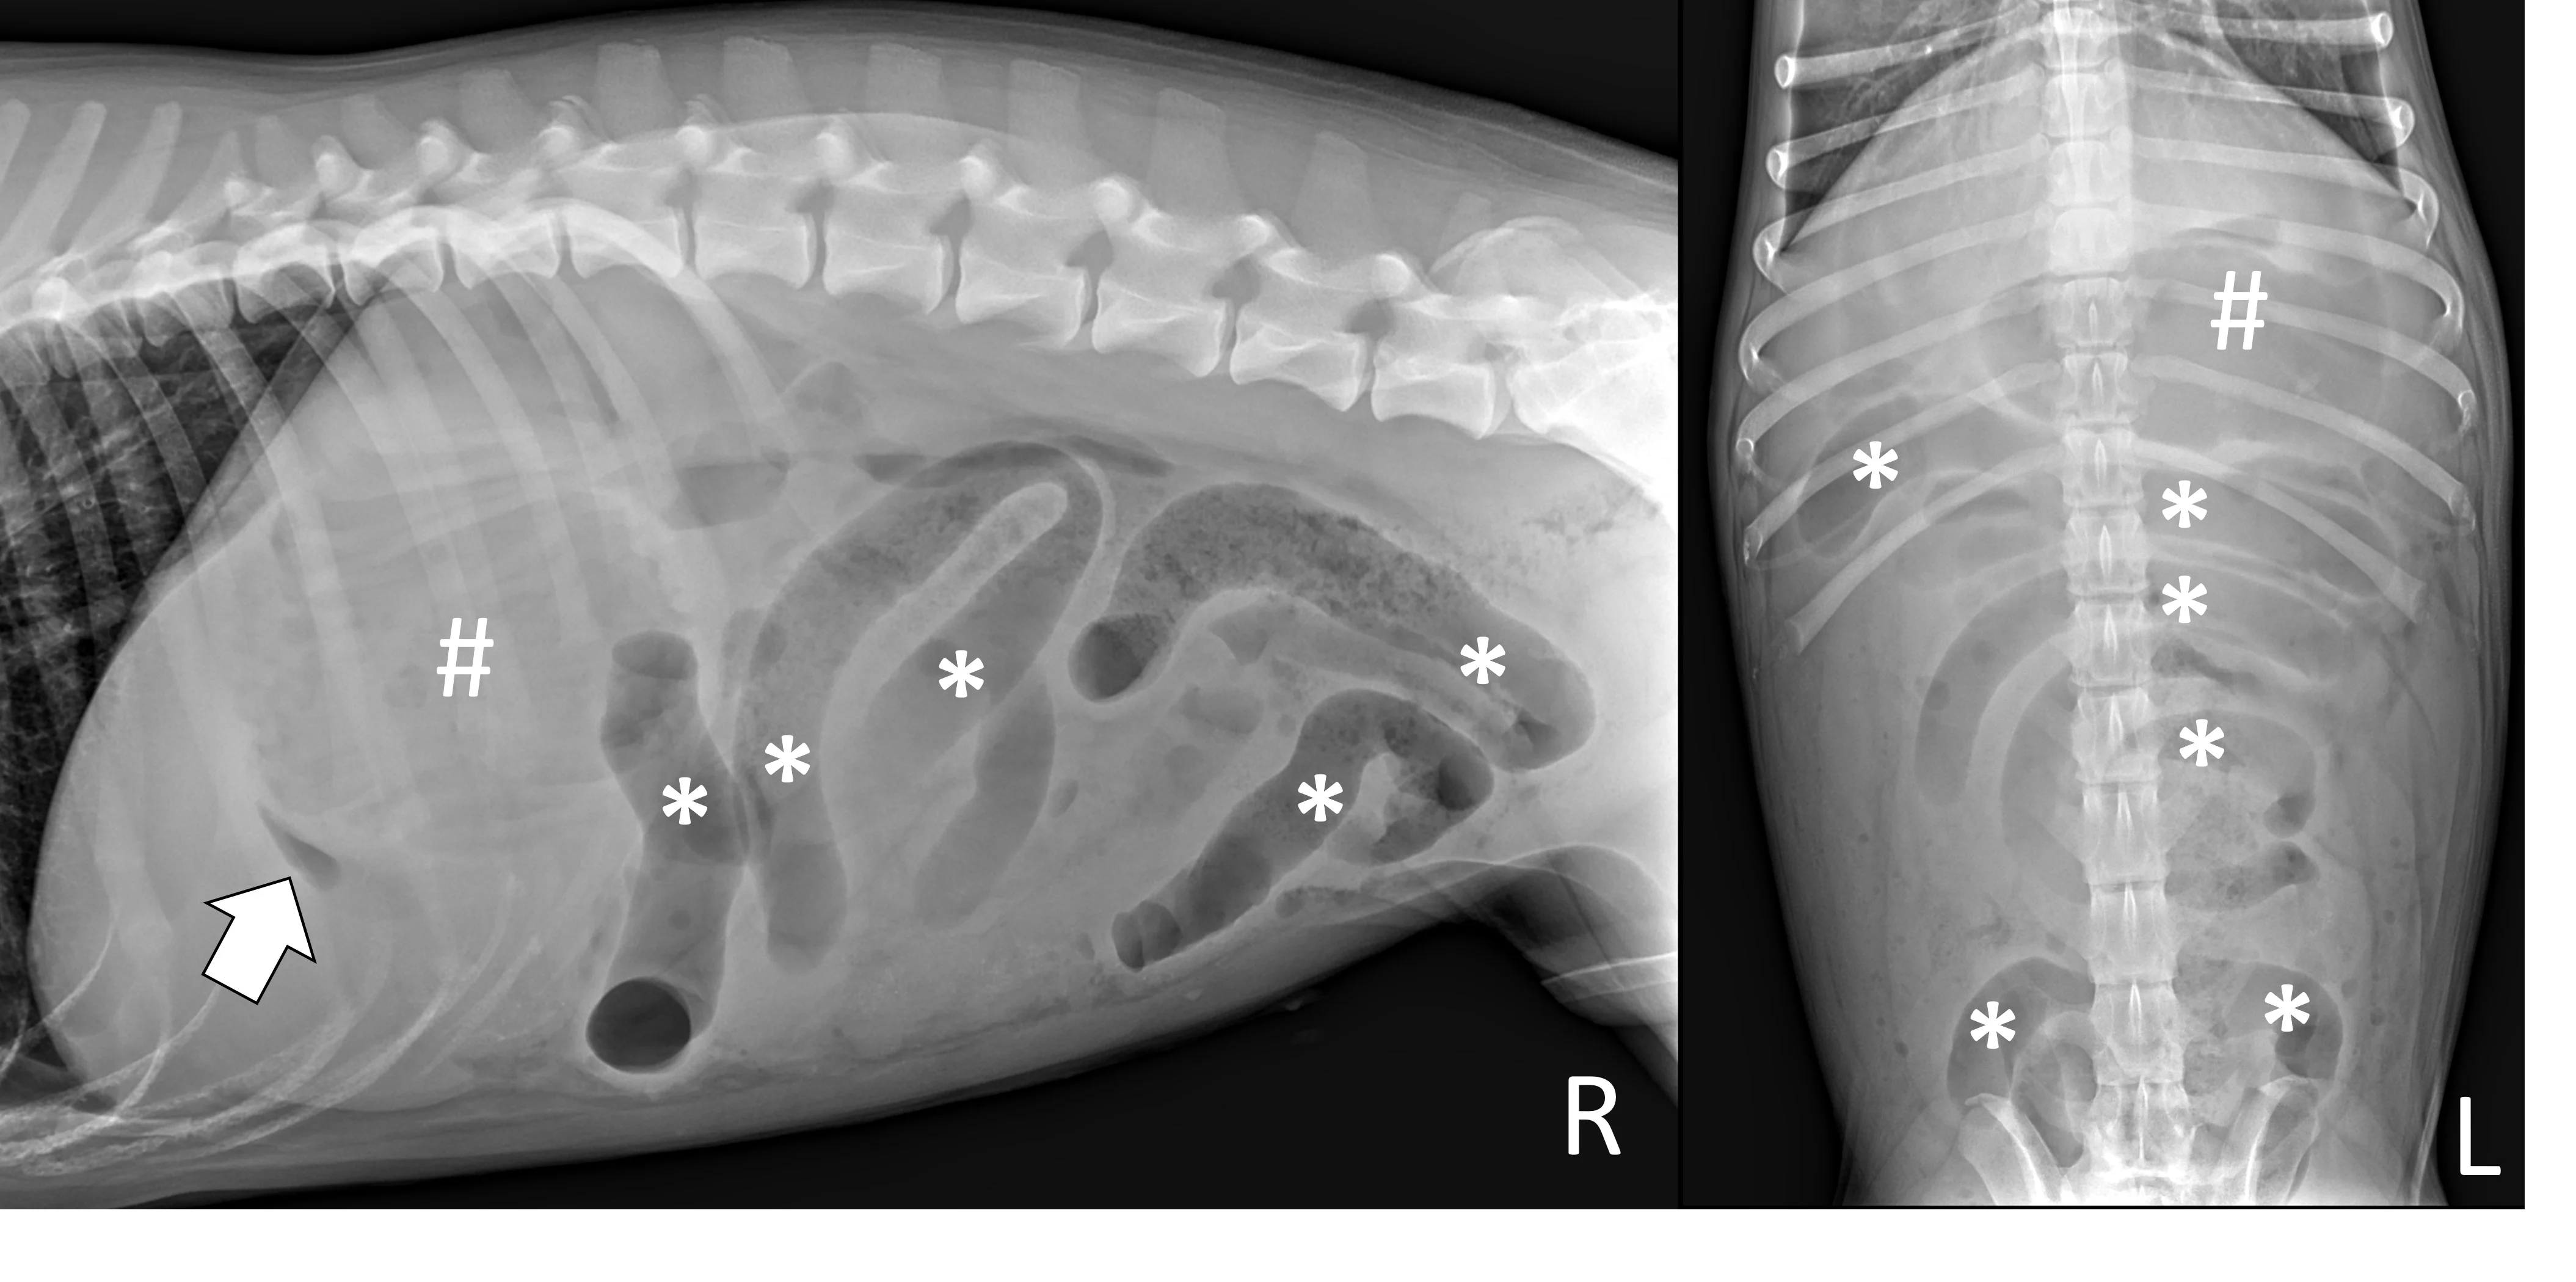

Pyloric Outflow Obstructions

Pyloric outflow obstructions occur when a foreign body lodges in the pyloric outflow tract or proximal duodenum and can cause variable gastric distention depending on the length of time the obstruction has occurred and whether the patient has recently vomited, as recent vomiting can reduce gastric size. Although exceptions are possible, acute complete obstructions typically cause mild to moderate gas dilation, and chronic partial obstructions can cause more moderate to severe dilation, predominately with fluid. A gravel sign, characterized by gravity-dependent mineralized ingesta often located in the pyloric antrum, is also possible with chronic partial obstructions (Figure 3).

Right lateral and ventrodorsal abdominal radiographs of a 2-year-old spayed Boston terrier with a chronic pyloric outflow obstruction secondary to a surgically confirmed foreign body in the proximal duodenum. The stomach is severely dilated, predominantly with fluid (pound signs). Mineral opaque material located ventrally is consistent with a gravel sign (arrow).